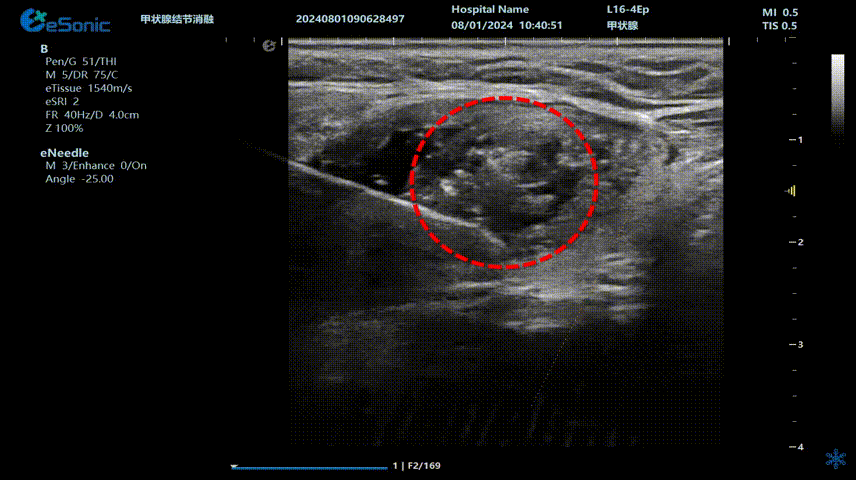

640 (3) (2).gif

(甲状腺结节射频消融动态视频)

李女士接受了甲状腺射频消融手术,过程顺利,手术耗时约20分钟,患者无出血、声音嘶哑等并发症。术后生命体征正常,观察几小时后便回家休息。次日恢复正常生活,颈部几乎看不到明显伤口。复查时显示甲状腺结节缩小,吞咽异物感消失。术后李女士摸着几乎无痕的颈部笑到:“没想到20分钟就解决了困扰我几年的问题!为微创射频消融技术点赞!”